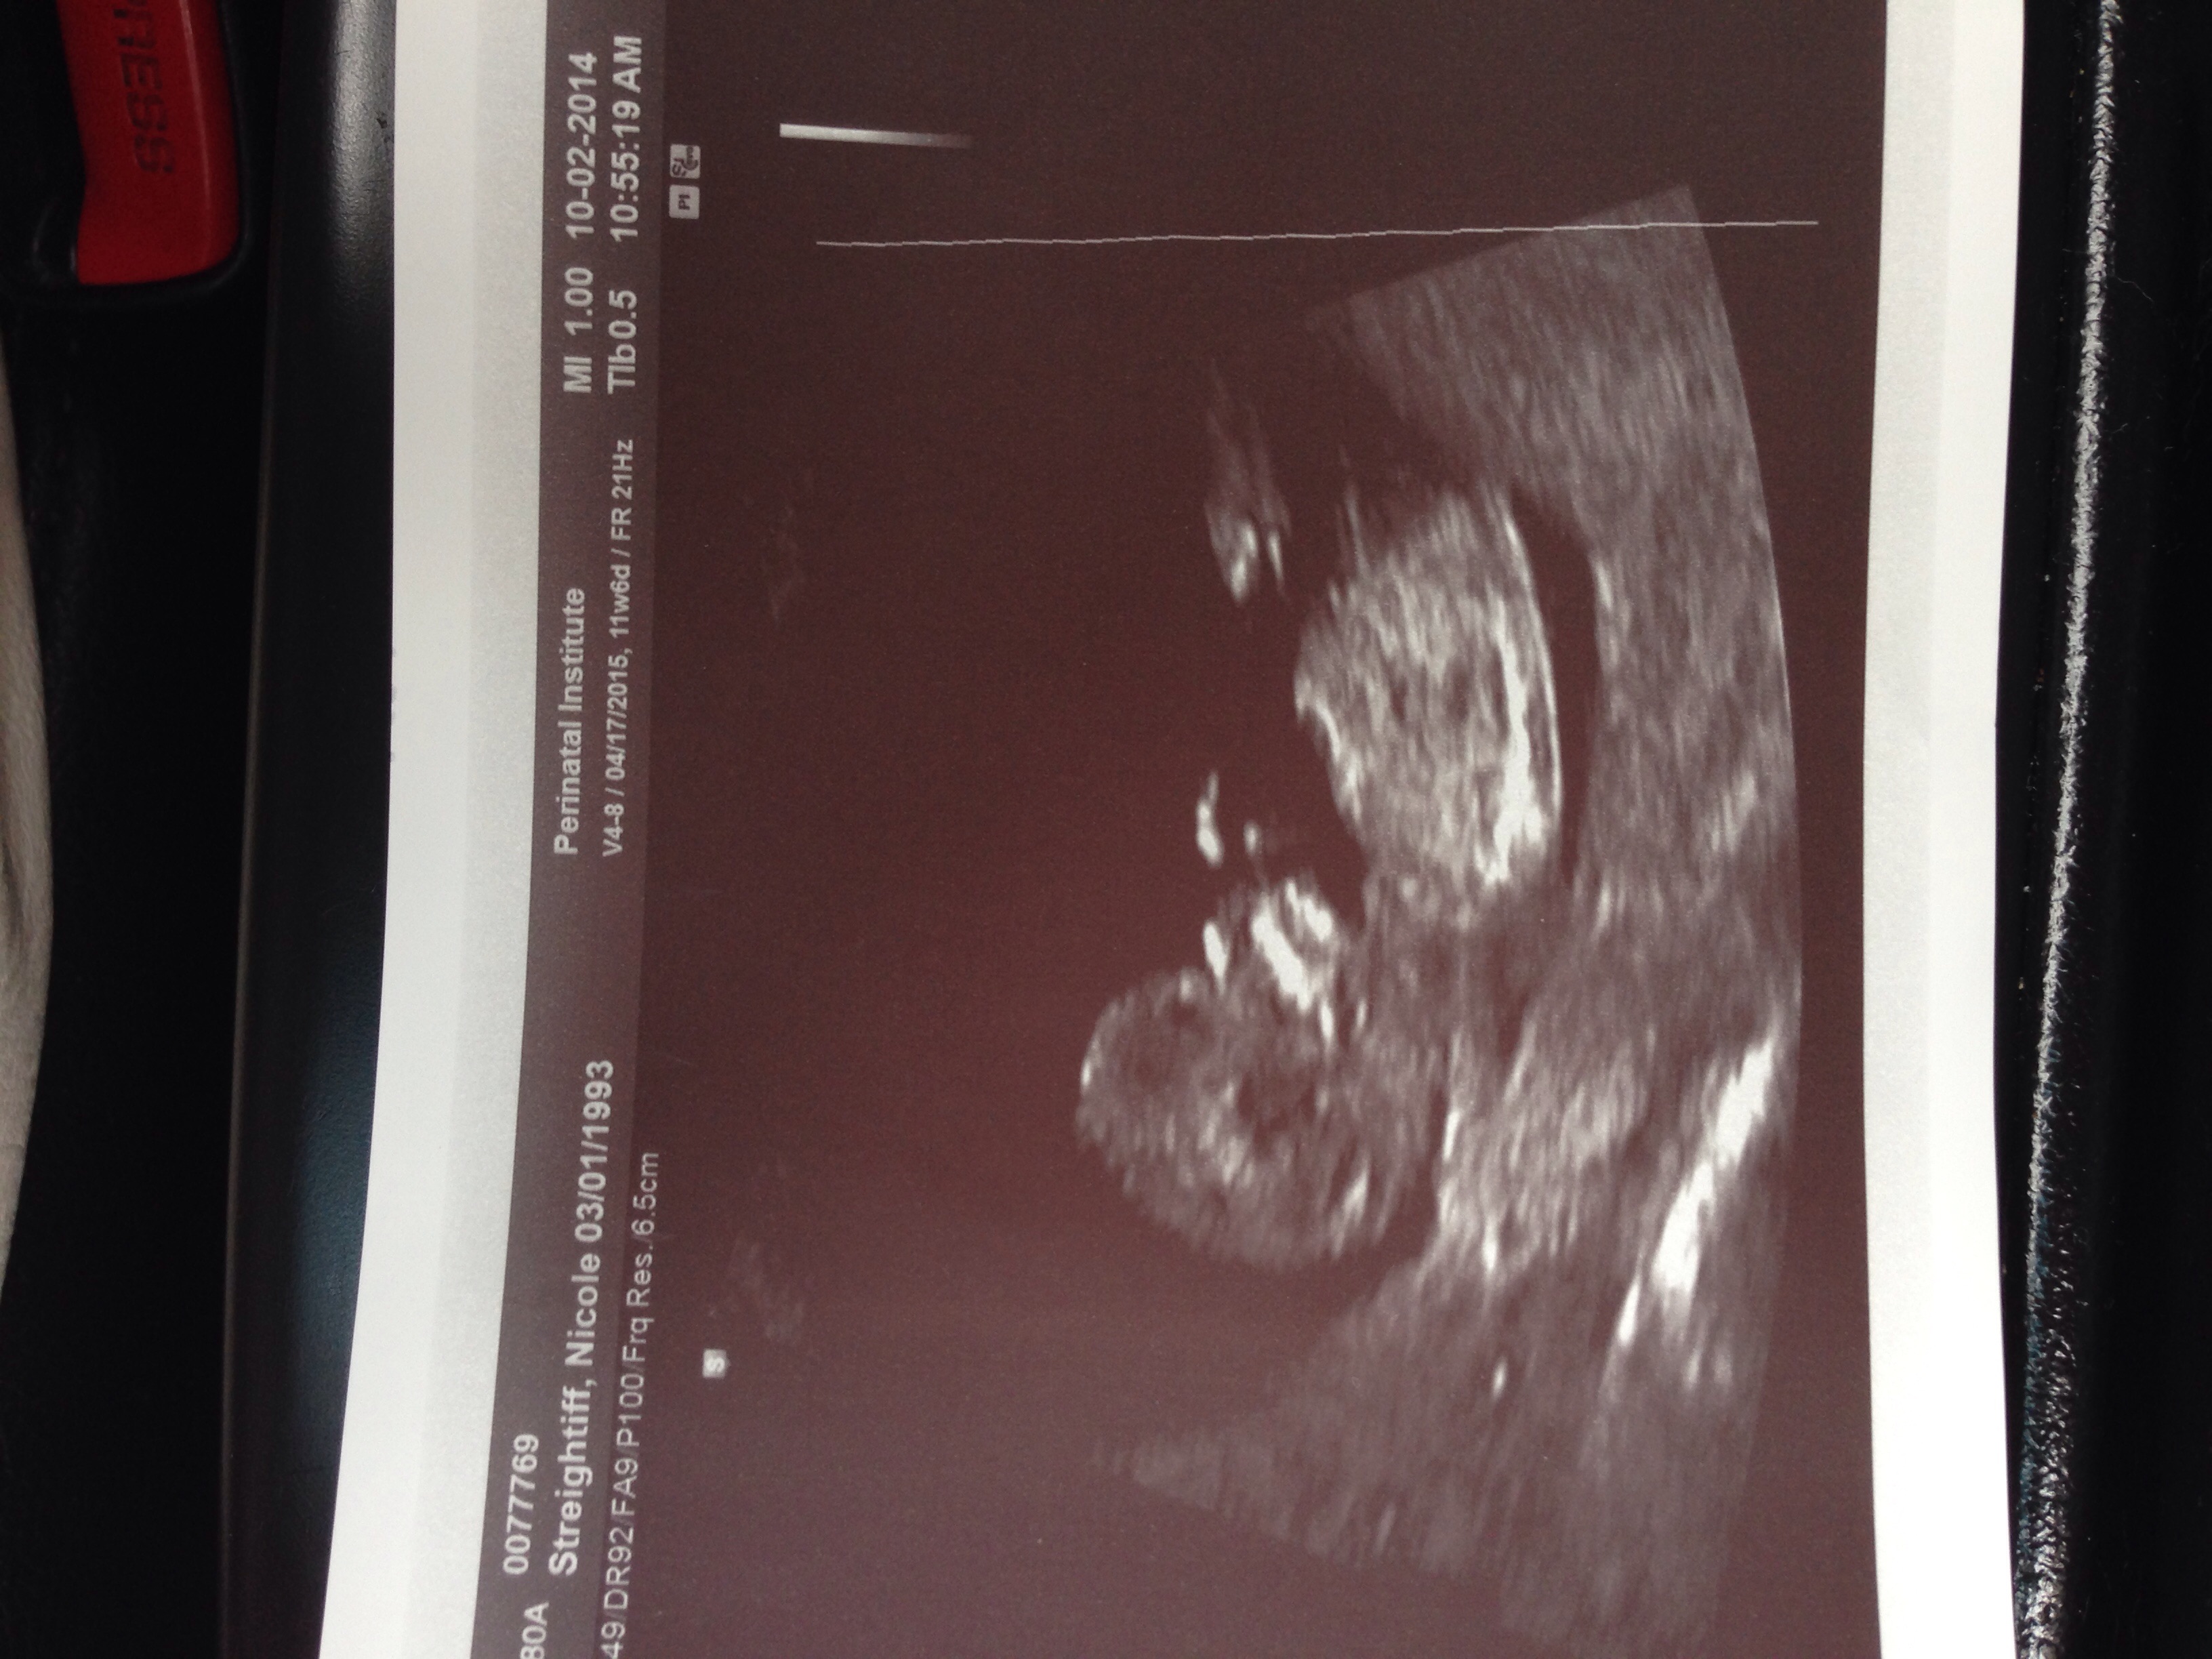

• I had mine last week! It was amazing. My little peanut was all about his/her thumb too. You can even see it in the ultra sound picture! I loved every second! Can't wait for my next ultra sound :)

There is way too much personal information on that ultrasound. And how is it possible that kids born in 93' are having kids? I graduated high school in 97. My God I'm old!

• Well it won't let me delete the picture. It's really not a big deal. It says my name and birth date. If I could take it down I would.